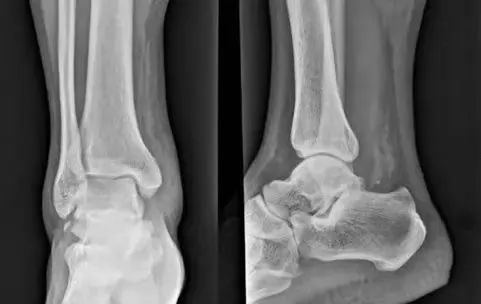

其中距腓前韧带是防止距骨向前移位的主要结构,该韧带最薄弱,踝关节内翻损伤中最容易伤及,可造成距骨止点处撕脱骨折。

踝内翻损伤造成距腓前韧带距骨止点处撕脱骨折

各类型撕脱骨折由于撕脱骨块较小或被重叠往往出现 X 表现的假阴性,另外由于患者不重视,未摄片检查以及采取不正当的处理措施,均容易遗漏撕脱骨折及韧带损伤的诊断。